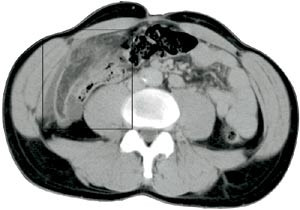

Pasient 2. En 42 år gammel mann, tidligere appendektomert og operert for etterfølgende adheranseileus, kom inn med konstante smerter i høyre nedre kvadrant av halvannet døgns varighet. Han hadde redusert matlyst, men ikke oppkast. Ved klinisk undersøkelse var han subfebril og hadde en palpabel oppfylling til høyre for umbilicus og tegn til peritonitt. Ultrasonografi viste, svarende til palpasjonsfunnet, en ekkorik, relativt homogen oppfylling med et par små sentrale hypoekkoiske foci. Den var velavgrenset fra tarm, 3 x 8 cm stor og med litt ødem omkring (fig 3). CT fremstilte i samme lokalisasjon en skarpt avgrenset lavattenuerende, inhomogen oval oppfylling med omliggende ødem. Den var 10 x 4 cm stor og hadde utseende som ødematøst fettvev (fig 4). Røntgen thorax og oversikt abdomen var upåfallende. Preoperativ diagnose var uspesifisert oppfylling eller infiltrat, sannsynligvis uten relasjon til tarm. Pasienten ble laparotomert, og det ble funnet torsjon av en del av omentet, med begynnende nekrose. Affisert fettvev ble fjernet og diagnosen verifisert ved histologisk undersøkelse.

Intraabdominalt fokalt fettinfarkt fremstilles ved CT som en velavgrenset oppfylling med fettattenuasjon av noe høyere tetthet enn normalt peritonealt fettvev (ca. -60 Hounsfield-enheter versus -120 Hounsfield-enheter) (1, 2, 6) – (9). I fettoppfyllingen ses høyattenuerende linjer eller drag arrangert i konsentrisk eller spiralaktig mønster (oftest kalt «stranding») og eventuelt mer veldefinerte foci med høyere tetthet. Dette indikerer ødem og blødning. En liten mengde fri væske nær lesjonen er hyppig til stede. Som ved ultrasonografi kan man finne fortykkelse av tarmvegg og peritoneum og masseeffekt.

Hyperattenuerende perifert sjikt omkring lesjonen er også beskrevet, men da oppfattet som å være indikator for at epiploisk appendagitt foreligger (5, 8). Vår andre pasient med omentinfarkt fremviste delvis dette tegnet på CT (fig 4), men hos ham brukte man intravenøs kontrast, som kan ha gitt oppladning i inflammert peritoneum. Andre kriterier som kan gi mulighet for å skille mellom disse to entiteter, er størrelsen og relasjonen til colon. Infarkt av oment er større enn epiploisk appendagitt, og omentinfarkt befinner seg medialt for colon ascendens eller descendens, mens epiploisk appendagitt ligger anteriørt eller anterolateralt (8). Massen ved omentinfarkt er heterogen og oftest til høyre i abdomen, mens epiploisk appendagitt er mer homogen og hyppigst på venstre side (1, 8). I praksis har det liten betydning å skille disse to former for fettinfarkt, fordi det ikke foreligger overbevisende diskriminerende kriterier og fordi symptomatologi og behandling er lik. Det samme gjelder enten det foreligger torsjon av omentet eller primært infarkt (5).